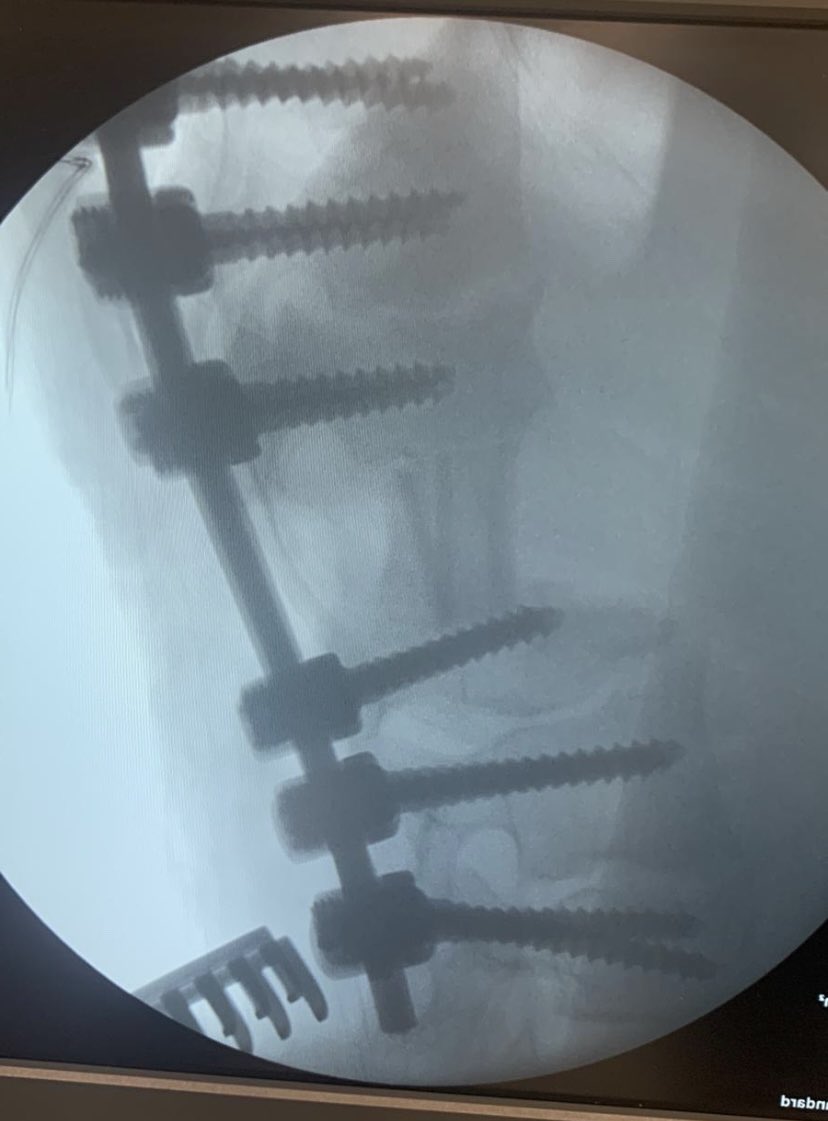

Male 40yo, healthy and physically active.

How do you treat this fracture?

Nonop, ORIF with plate or nailing?

@InvictaOrtho @traumaticum @rkh_md @Gnomelover1970 @aqueipot @DrMarecek

@DrBhavinJadav

#orthotwitter